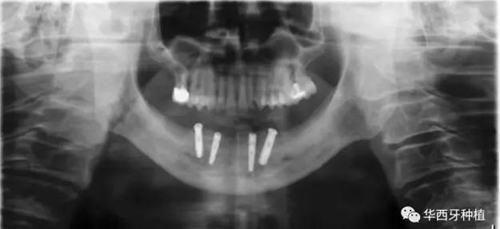

接下來吳教授分別針對幾種具有不同特征的病例,進行分析、設(shè)計與病例回顧。對于不同骨量缺失的全口牙缺失患者,可選的種植修復(fù)方式有較為傳統(tǒng)的組牙種植修復(fù)、種植覆蓋義齒修復(fù)、all-on-four或all-on-six的修復(fù)方式。拓寬了我們在全口牙缺失病例種植與修復(fù)治療中的視野與選擇。

對于骨質(zhì)較差的患者,種植覆蓋義齒修復(fù)與all-on-four或all-on-six修復(fù),則更為適合。

吳教授特別針對手術(shù)難度更大的all-on-four修復(fù)做了詳細的關(guān)于概念、設(shè)計、操作、修復(fù)的描述,首先是針對難度最大的手術(shù)環(huán)節(jié),就解剖、微創(chuàng)操作分別加以闡述。將他自己在臨床工作中的寶貴經(jīng)驗分享給了大家。